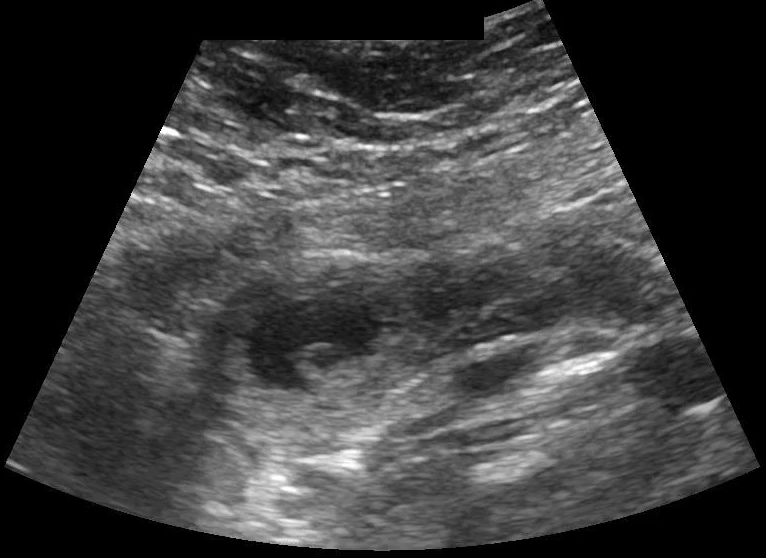

POCUS transabdominal revealed no free fluid in hepatorenal space (image 1), and the uterus without an intrauterine pregnancy (image 2) but with pelvic free fluid (image 3). The left adnexa revealed a gestational sac with a yolk sac (image 4), diagnostic for an ectopic gestation.

Image 1: Hepatorenal space, caudal edge of liver without free fluid.